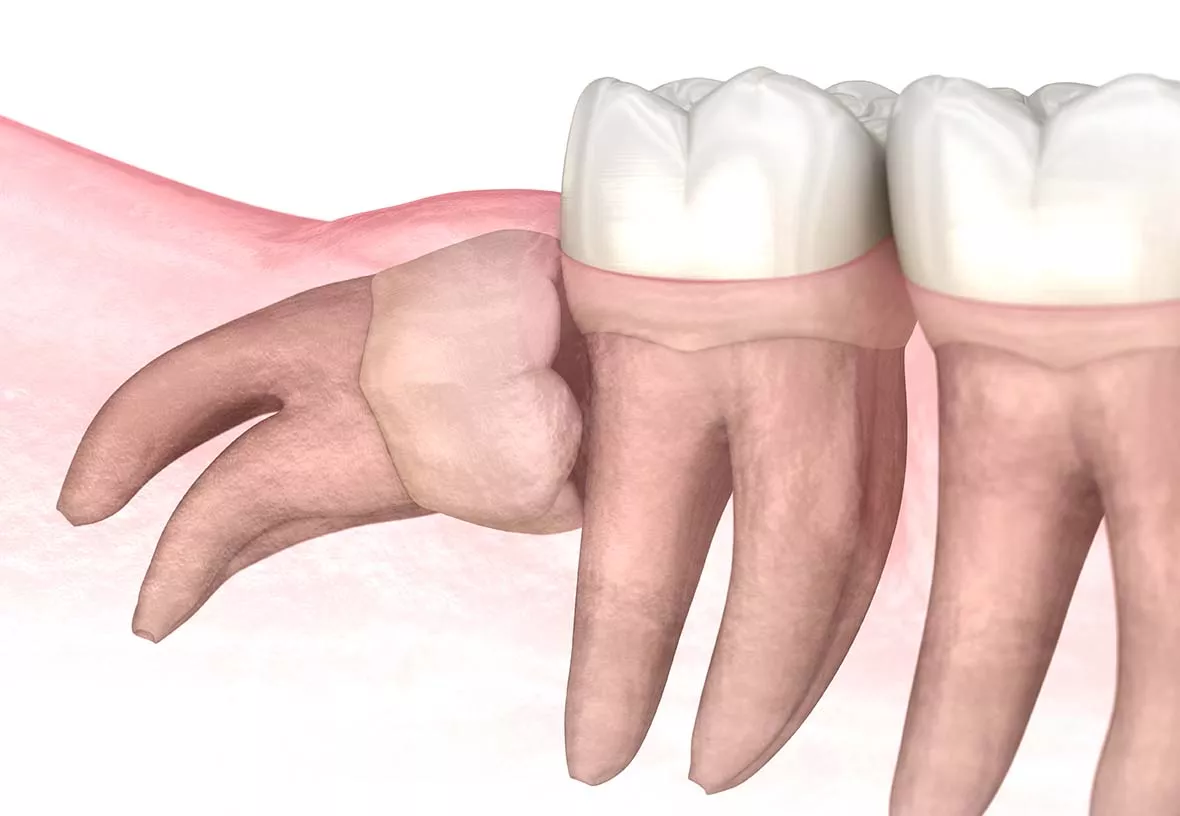

The wisdom teeth are usually removed before they break through the gums. That means they need to be removed through surgery. Your dentist will make incisions near each tooth and then remove them. The treatment is done with a local anesthetic (freezing), and your dentist may also give you a mild sedative to help you stay relaxed during the procedure. After your wisdom teeth are removed, your dentist will close the incisions with sutures. You will need to return to your dentist’s office in about a week to have the sutures removed.